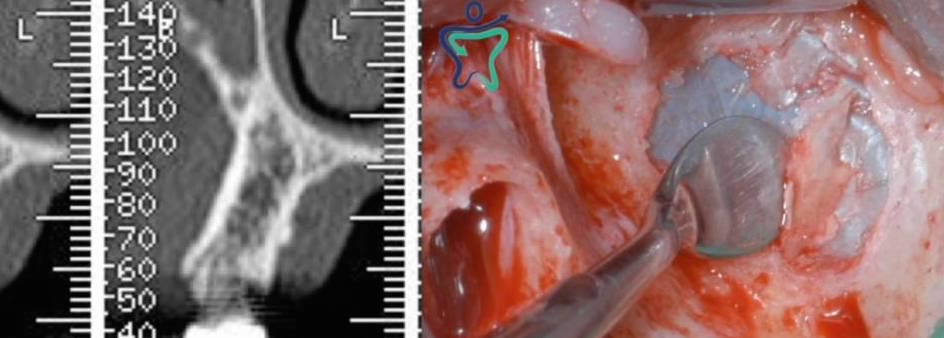

• Grande rialzo del seno mascellare con approccio laterale

Come pianificare la chirurgia implantare?

Lo scoprirai all'interno di questo modulo.